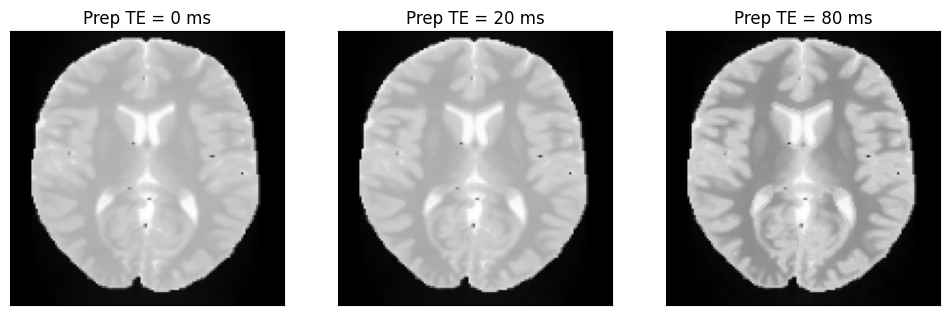

We can now plot the images with different T2-preparation times.

idat = idata.data.abs().numpy().squeeze()

fig, ax = plt.subplots(1, idat.shape[0], figsize=(4 * idat.shape[0], 4))

for i in range(idat.shape[0]):

ax[i].imshow(idat[i, :, :], cmap='gray')

ax[i].set_title(f'Prep TE = {int(t2_prep_echo_times[i] * 1000)} ms')

ax[i].set_xticks([])

ax[i].set_yticks([])

_images/e415cddc1f2cfa0e30145ac295ab0f2c5ab9d56828e56576d831d57987174686.png